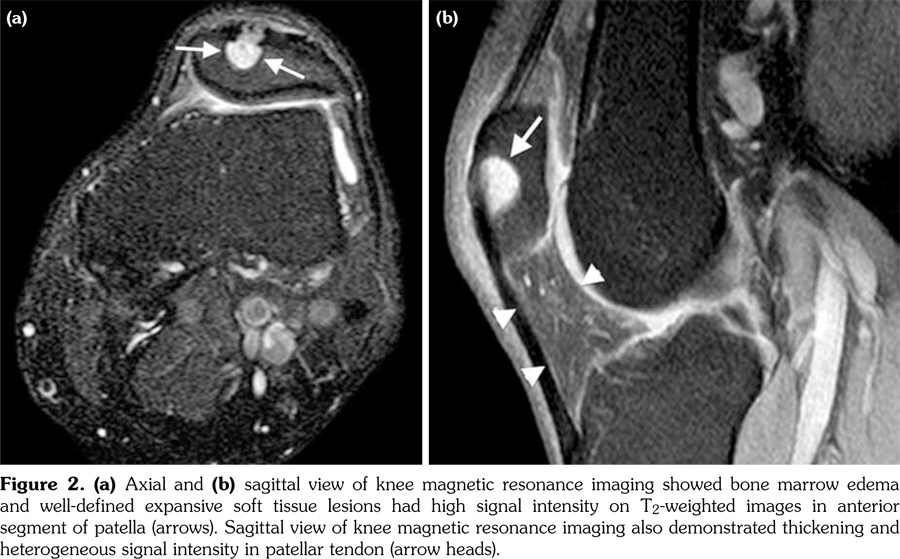

Laboratory tests including erythrocyte sedimentation rate, blood biochemistry, rheumatoid factor, anti-cyclic citrullinated peptide, liver function tests, and urinary analysis were normal except for uric acid value of 7.9 mg/dL (normal range 2.6-6.0 mg/dL) and C-reactive protein value of 2.1 mg/dL (normal range 0.01-0.82 mg/dL). Roentgenogram revealed lobulated, well-defined expansive osteolytic lesion with sclerotic rim at the anterior border of both patellae. The lesion in the right patella was 2x2.5 cm and the lesion in the left patella was 3x3 cm in diameter (Figure 1). Subsequent knee magnetic resonance imaging (MRI) showed bone marrow edema and well-defined expansive soft tissue lesions with low signal intensity on T1-weighted and high signal intensity on T2-weighted images (Figure 2a) in the anterior segments of the both patellae. Sagittal sequences demonstrated thickening and heterogeneous signal intensity in both patellar tendons (Figure 2b). The diagnosis of gouty involvement of the patella and patellar tendon was established according to the clinical, laboratory, and radiological findings. The patient was treated with colchicine 1 mg/day, and methylprednisolone 8 mg/day. Pain decreased in two weeks and he was able to resume his daily living activities more easily. Allopurinol 300 mg/day was started as urate-lowering therapy. Patient is under follow-up for five months and his serum uric acid level is 5.9 mg/dL.

Plain radiographic features of gout include soft tissue swelling and bony erosions. These features are generally normal in early gout.(4,12) MRI is critical for assessing abnormalities in bones, ligaments, and tendons within joints. MRI findings in these patients included bone marrow edema, tophi deposition of patella, and heterogeneous signal intensity in both patellar tendons. These findings are compatible with those of previous studies.(6,13) Such deposits present as masses with low signal intensity on T1 and intermediate to high signal intensity on T2-weighted images due to the presence of uric acid deposition and associated inflammation.(13,14) Differential diagnosis also includes chronic rheumatoid arthritis, pigmented villonodular synovitis, chronic infectious arthritis, and amyloidosis. The constellation of clinical and MRI findings often allow the specific diagnosis to be rendered.(15)